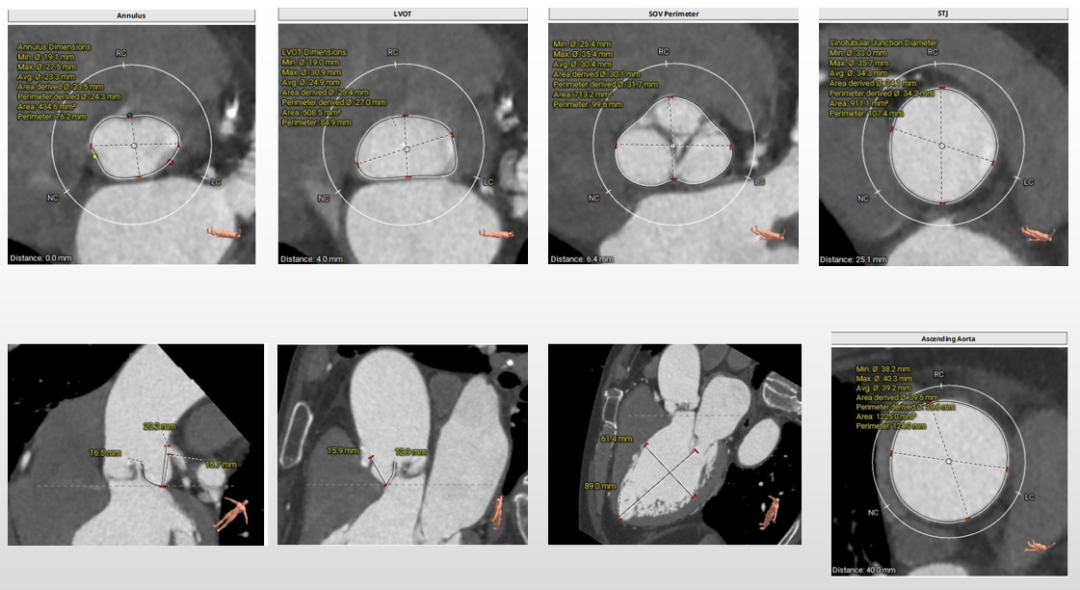

第一例术前评估

主动脉根部评估

三叶式主动脉瓣,瓣叶增厚,流出道呈敞口状,左右冠均有钙化,由于瓦氏窦、STJ内径小,左冠窦瓣叶长度>瓣叶附着缘到冠脉开口的距离,VTC3.1mm,术中冠脉阻挡风险较高。

瓣环上解剖结构评估

中度钙化,瓣上6-8mm限制最重,根据瓣环及瓣上情况,选18mm球囊预扩、AV23瓣膜。

外周血管及主动脉弓解剖

双侧髂总动脉轻度扭曲少量钙化,腹主动脉折角明显,入路血管直径尚可,选择右侧为主入路,左侧为辅入路。